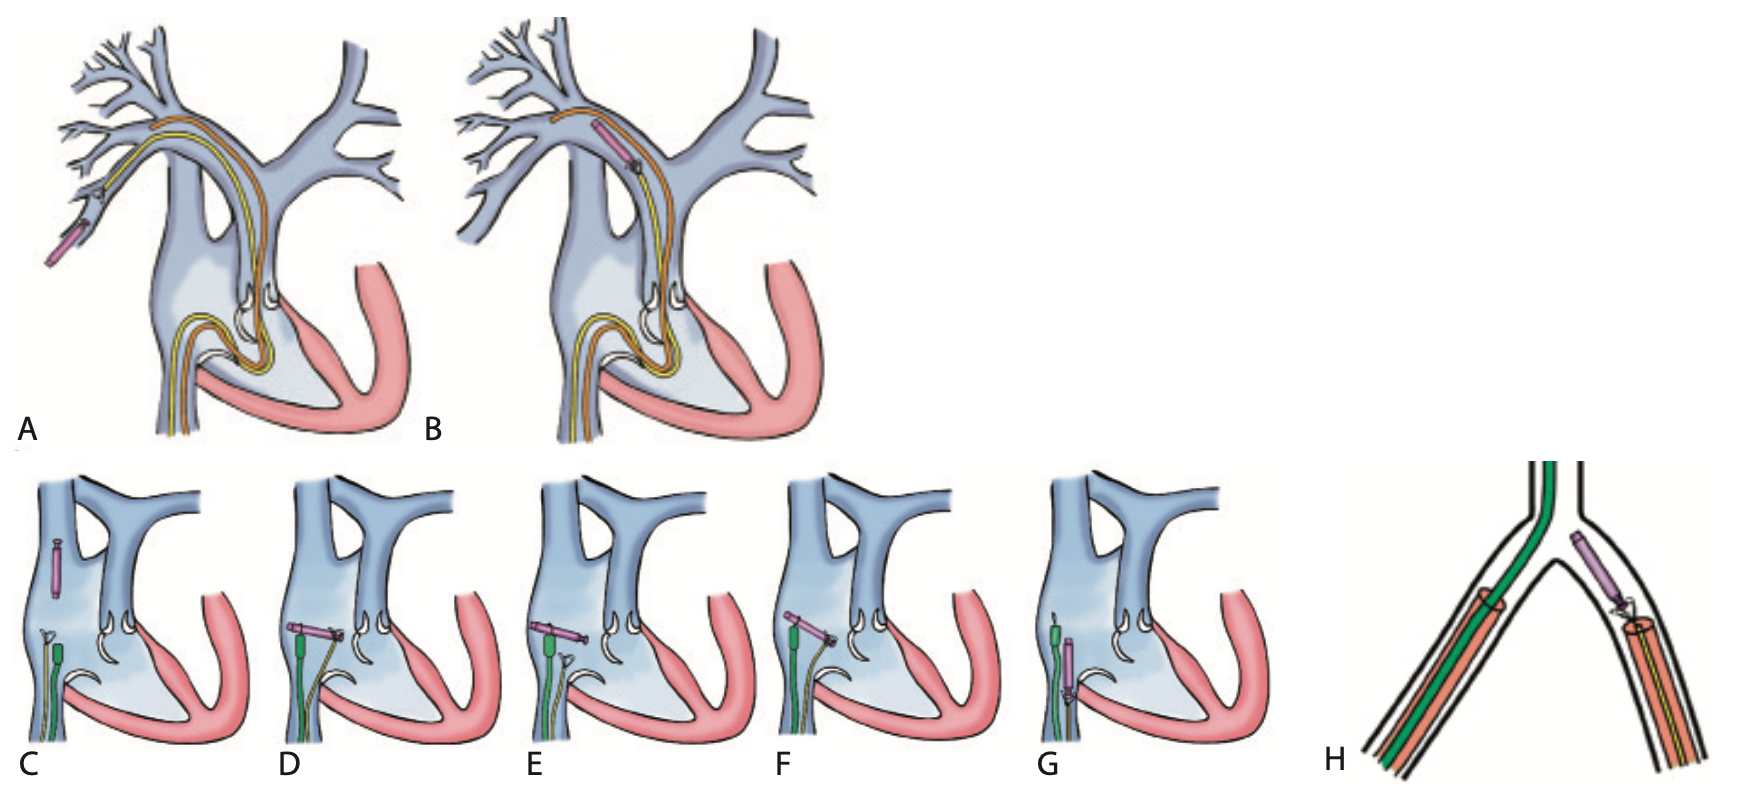

(A) The leadless pacer with docking button proximal to the EN Snare device. Also shown is the 6 French (F) diagnostic catheter used for angiography. (B) The lead- less pacer captured and retracted into main pulmonary artery by the EN Snare device. (C) The failed attempt to switch the leadless pacer from the EN Snare to the NRC catheter. Consequently, the pacer floated into the superior vena cava (SVC) with the docking button positioned distally. (D) The pacer was recaptured by the EN Snare device from the SVC, brought into the right atrium, and captured by the NRC at the other end to attempt the switch. (E) We were unable to maneuver the screw-in end into the safety sheath of the NRC. (F) The NRC approach was abandoned, and the pacer was recaptured and removed from the NRC system with the snare from the docking end. (G) The pacer was wrestled free from the right atrium and removed through the inferior vena cava (IVC). (H) The pacer suc- cessfully lodged within the 18F sheath in the common femoral vein.

The patient was brought into the hybrid operating room and intubated after general anesthesia was administered. A pre-extraction pulmonary angiography was performed through a multipurpose catheter, ruling out any perforation or bleed (Figure 2 shows actual images of the pacer retrieval procedure and Figure 3 features a schematic of the sequence). An 18-30 mm EN Snare catheter (Merit Medical) was then advanced to capture the docking button on the leadless pacemaker. When the pacer was in the main pulmonary artery, another angiogram confirmed no perforation or vessel rupture, but did reveal an embolized branch of the distal vessel. The Nanostim Retrieval Catheter (NRC) (Abbott) was steered into the right atrium while the EN Snare, along with captured device, was retracted into the right atrium. Following the Nanostim device instructions for use (IFU), we next needed to switch the device from the EN Snare catheter to the NRC before retracting the device via the inferior vena cava (IVC). We released the device from the EN Snare, but before we could capture the device with the NRC, the pacemaker moved into the superior vena cava (SVC). The docking button was positioned toward the cranial aspect of the SVC, complicating plans to use the NRC. The EN Snare was used again and advanced up the SVC. We were able to successfully capture the leadless pacemaker by advancing the EN Snare loop over the body of the device and returned the device to the right atrium. On the second attempt, the pacer was released from the EN Snare and captured by the NRC. The NRC snare loop became fixed around the body of the device, and despite multiple attempts, we were unable to move the loop to the docking button or align the device in a coaxial fashion to the NRC. Plans to use the NRC were abandoned and the pacer pulled out of the NRC loop snare as the EN Snare loop was able to capture the docking button. The EN Snare catheter, along with the captured device, were withdrawn in an 18 French (F) sheath and retracted all the way to the hub. Since we had not used a Perclose system (Abbott Vascular) and the patient was heparinized, we decided to reintroduce a new sheath. The sheath with the embedded device was retracted 4 inches, nicked to introduce a 150 cm, .035-inch J wire, and a new 18F sheath was exchanged for later manual removal. The device was extracted from the sheath and sent to the company for analysis.